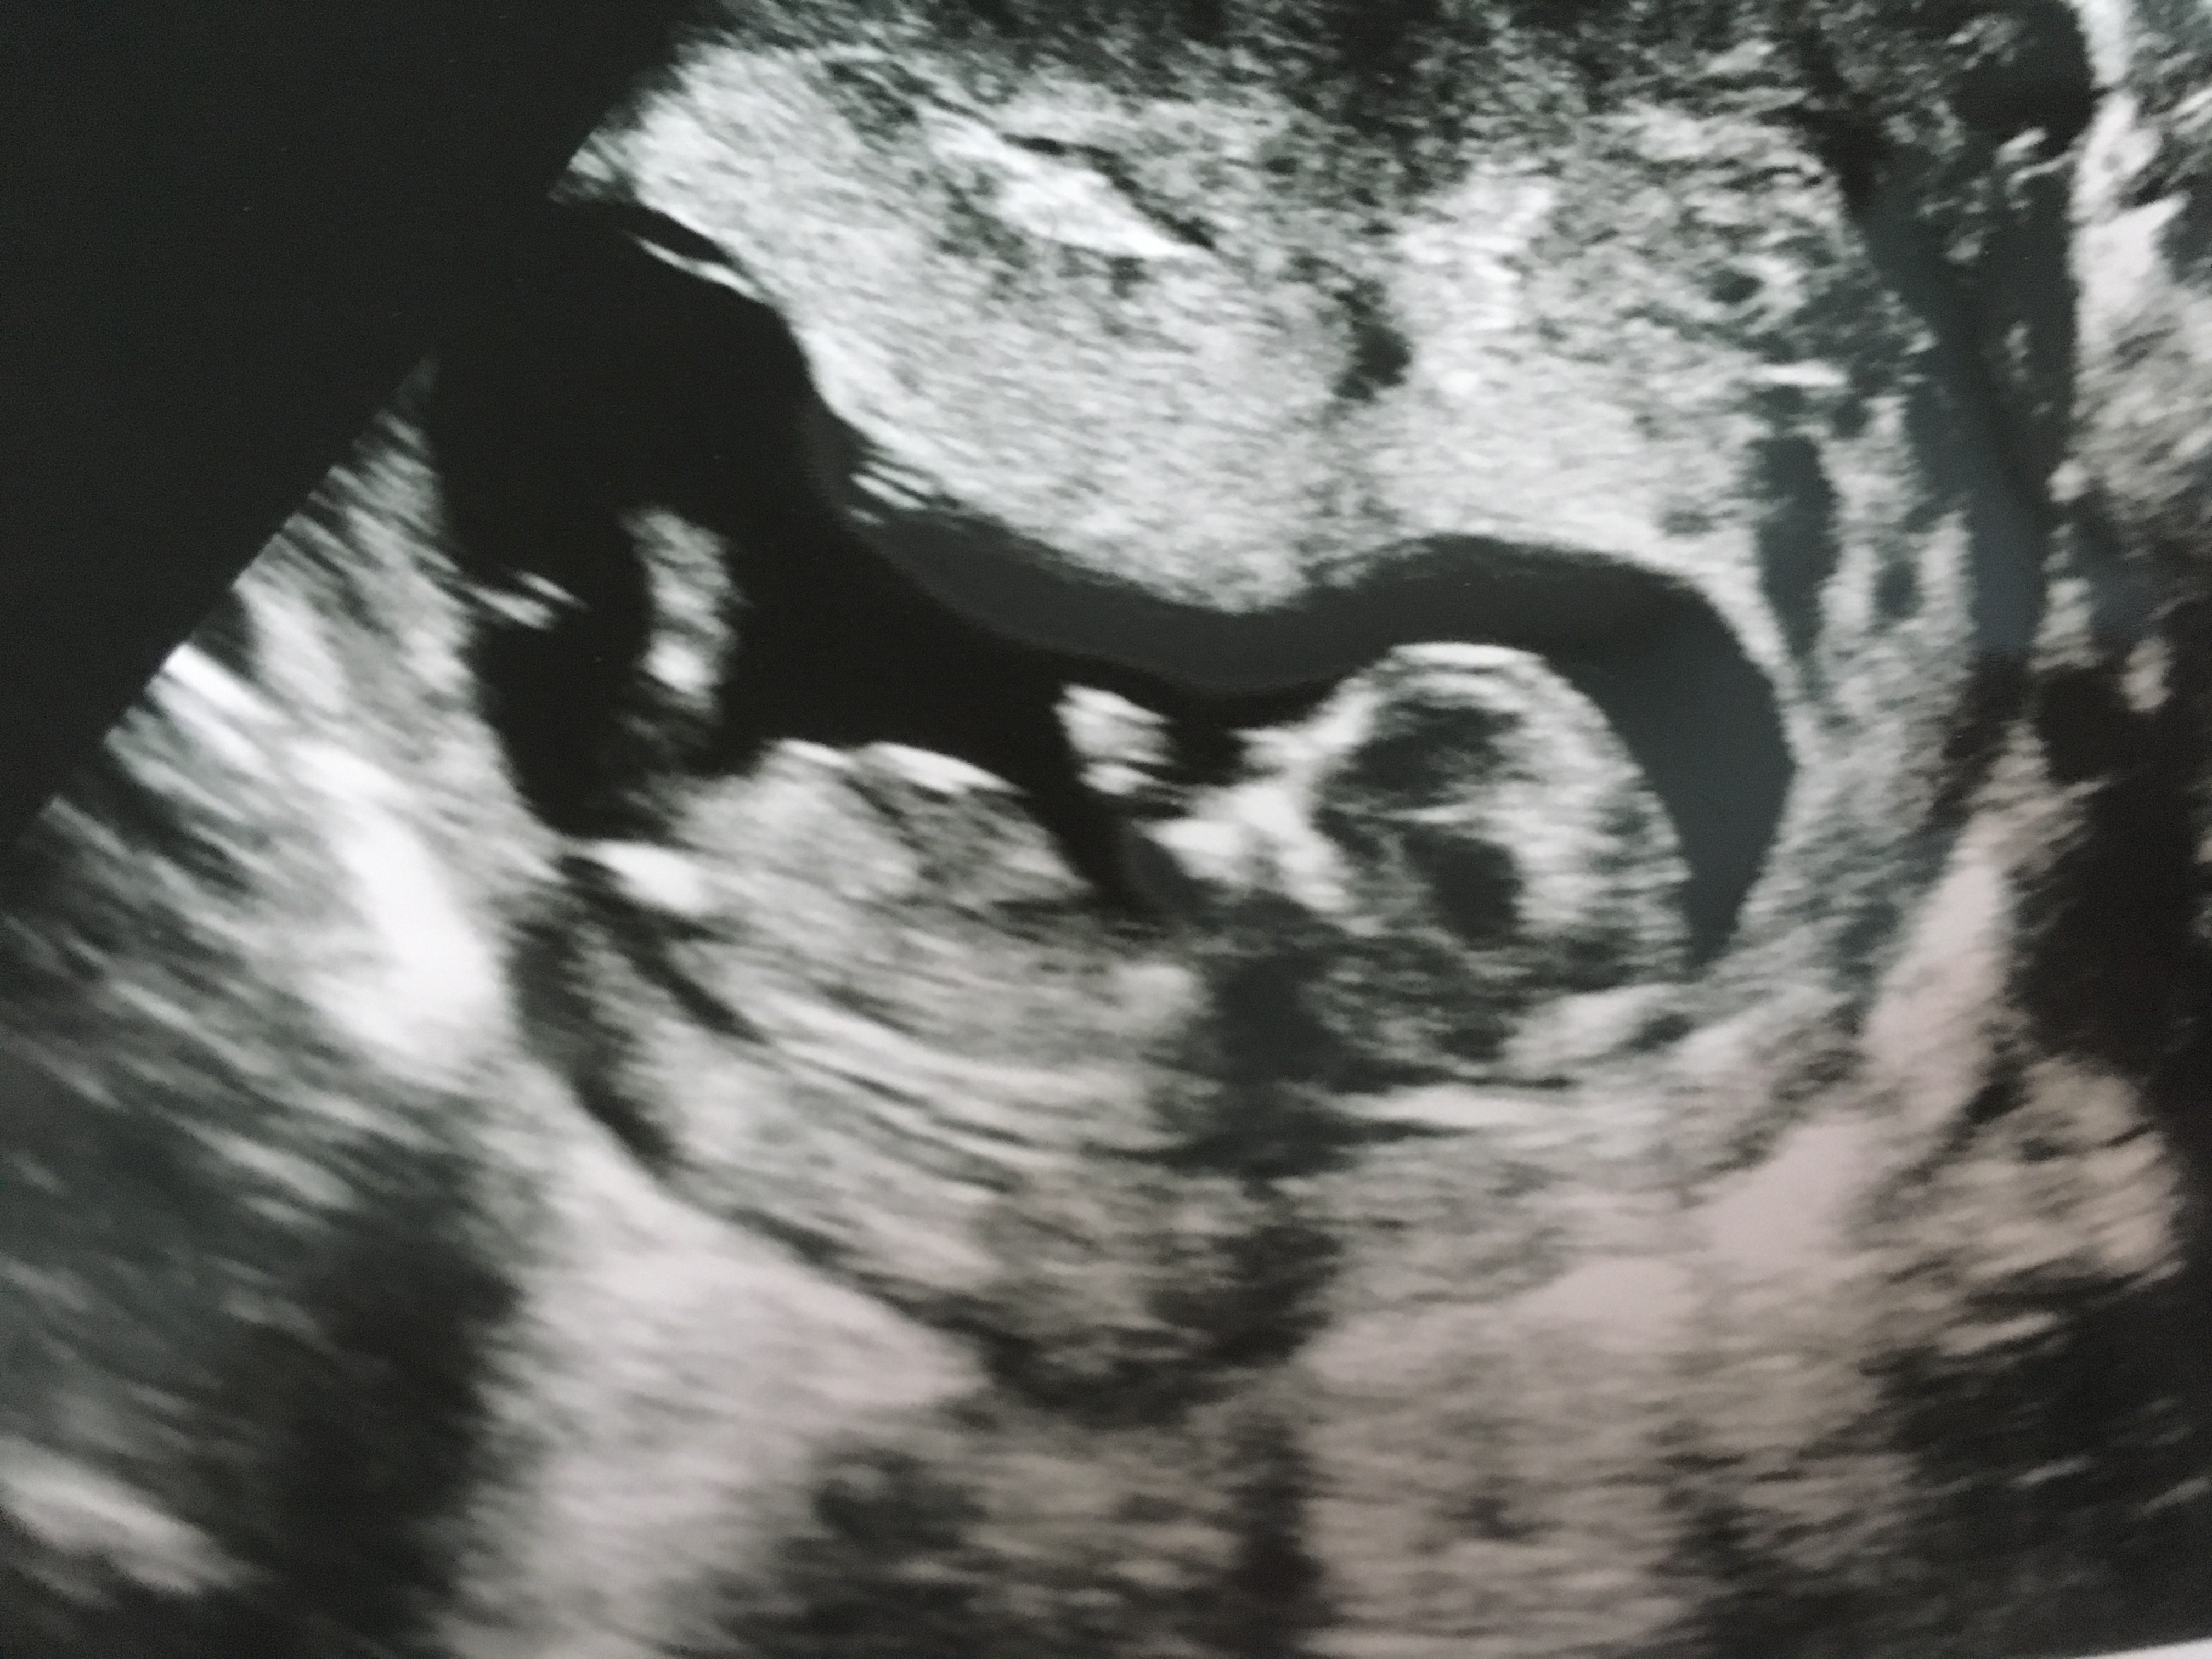

Hi everyone! Please let me know your nub guesses on my 12 week 2 day ultrasound. I'm not sure if any of these pics show the nub so I'm going to post a few of them. Thanks!! :)